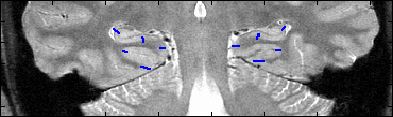

This is an example of one subjects demarcation. The A/P slice is slice

3.

4